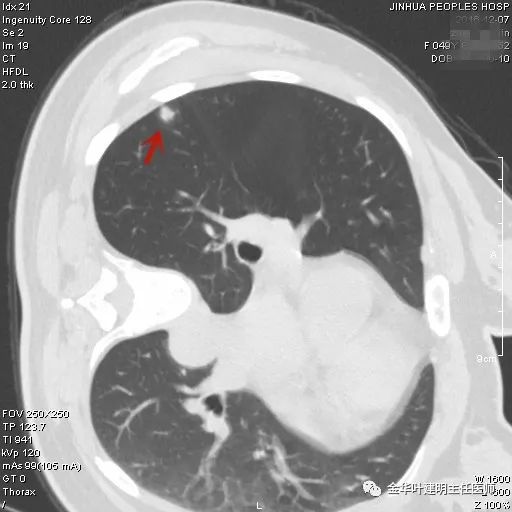

上图示胶原结节。我的理解是较慢性炎更向纤维瘢痕钙化发展,但仍未达钙化程度的一种状态(我不知道病理是不是这样)。该病灶表现为小而密度高的结节,边缘清晰,邻近胸膜却不牵拉,没有收缩力。